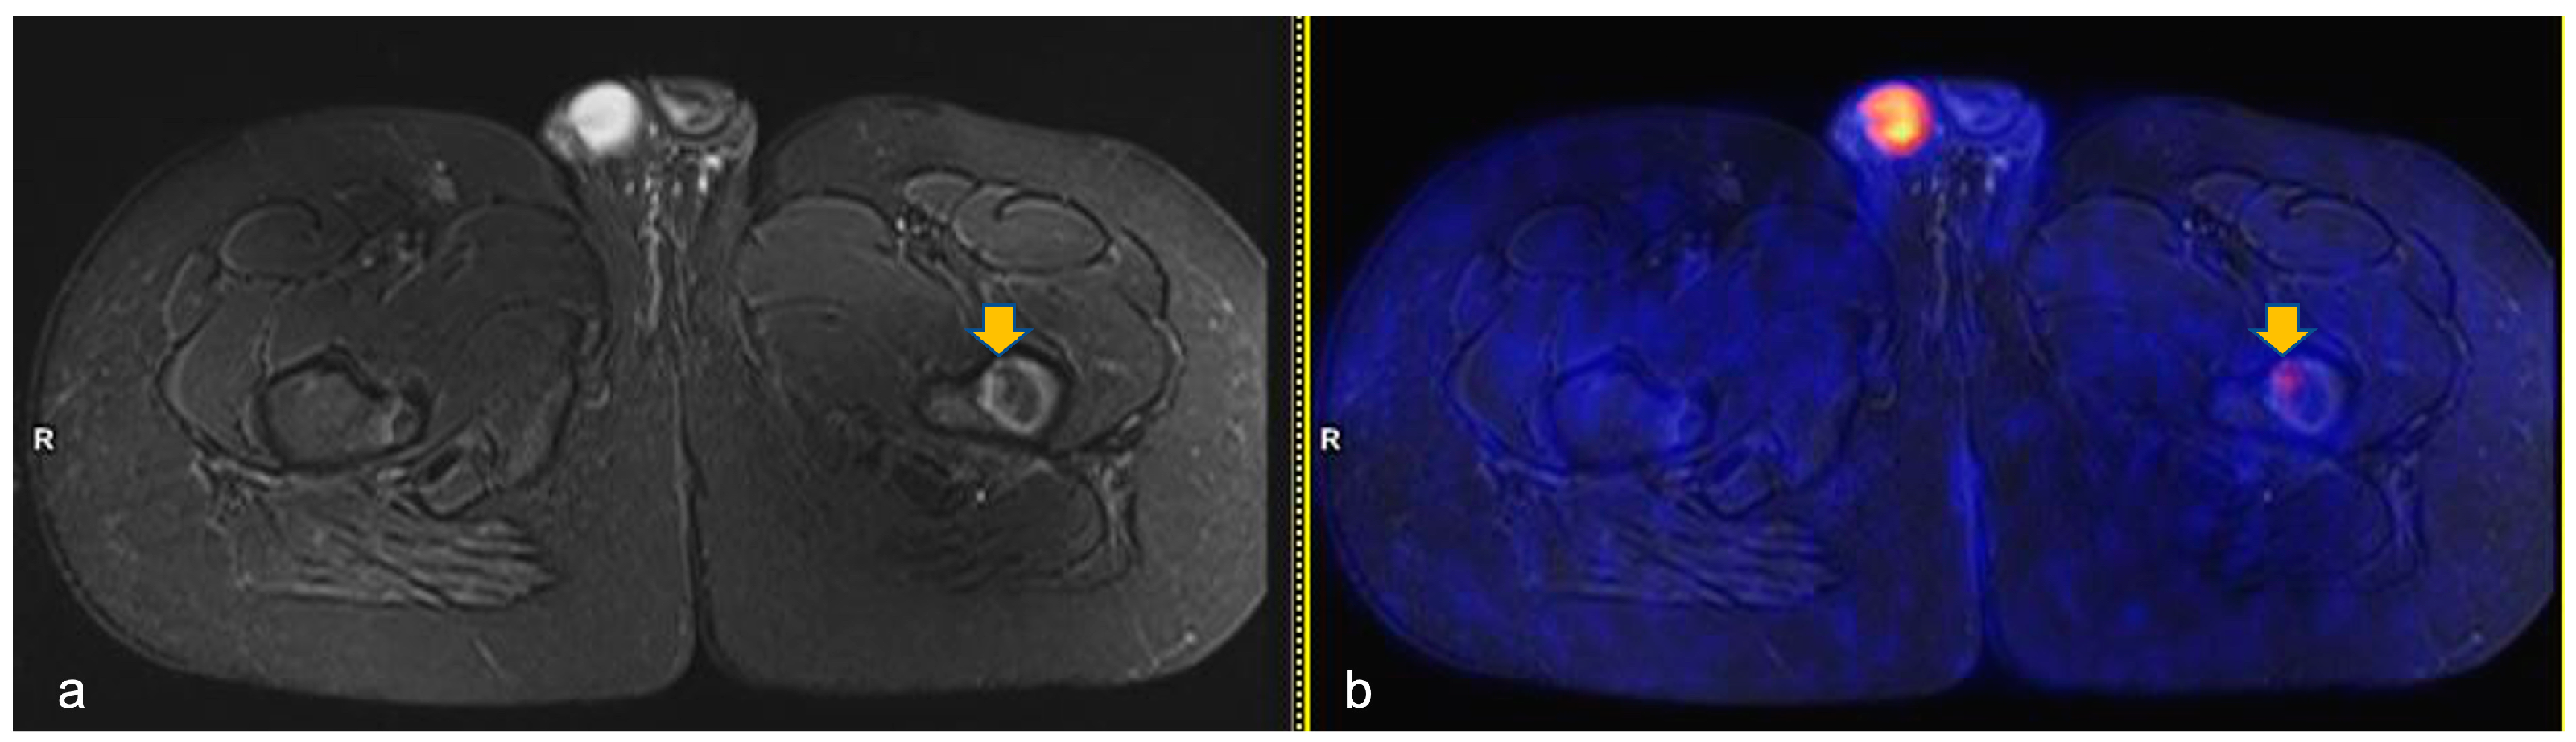

| Pts | TL | HL Disease Bone Involvement at Diagnosis | BILs Site Involvement | N. of Lesions | PET-MR Time-Point |

|---|---|---|---|---|---|

| 1 | 3 | Yes | bilateral distal femur diaphysis; right proximal tibia metaphysis and left proximal tibia diaphysis | 4 | ERA PET-MR |

| 6 | 3 | Yes | left proximal tibia epiphysis; left proximal femur diaphysis | 2 | ERA PET-MR |

| 8 | 2 | No | left distal femoral diaphysis | 1 | ERA PET-MR |

| 9 | 2 | No | mid-proximal left femur diaphysis; left proximal humerus metaphysis | 2 | ERA PET-MR |